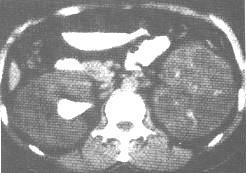

多囊腎 CT掃描 |

3、CT掃描:在過去用於確診多囊腎的非侵入性診斷技術中,CT是最理想的。多發囊腫薄薄囊壁內充滿的囊液及較正常增大了的腎臟,使這一成像方式在確診時極為精確(95%)。

多囊腎 CT掃描